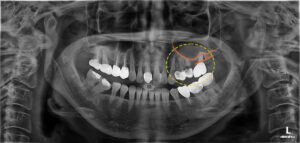

위 환자분은 왼쪽 보철물들이

음식물을 먹을 때 마다 불편하고

흔들린다고 하셨는데요. 😭

파노라마 사진을 촬영해보았더니,

앞쪽에 위치하고 있던 대구치는 빠진지 오래 되었고

뒷쪽 큰 어금니 하나에 두개의 크라운으로 제작하여

한 치아가 두 치아의 역할을 하고 있었어요.

또한 앞쪽 작은 어금니 두 치아는

치근이 파절되어 있고 치아 뿌리까지

우식이 진행되어 살리기 힘든 상황이었는데요.

결론적으로 구치부 세 치아 모두

발치가 진행되어야 했어요..